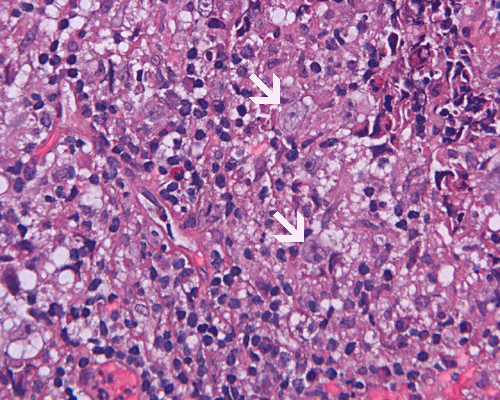

Paraffin sections: The entire volume of the tissue is made up of a granulomatous inflammation with poorly formed granuloma (Panel F, G, and H). The density of the lymphocytes is variable in different areas. In some areas, there is a rather intense lymphocytic infiltration accompanied by scant atypical cells with enlarged nulcei and prominent nucleoli (arrows in Panel I and J, Panel J is a higher magnification of Panel I). These atypical cells are quite easy to be missed. No microorganisms were identified by acid fast stain, PAS stain or GMS stain. The lymphocytes but not the atypical cells are positive for CD20 (Panel K) or CD3 (Panel L). The granulomatous background is strongly positive for CD68 (Panel M). Only rather faint positive staining for placental alkaline phosphatase (PLAP) is demonstrated and the interpretation is difficult as they are present in areas with crush artifact (Panel N). Many of the large, atypical cells are positive for CD117 (c-kit) (Panel O).

Intracranial germinoma is histologically identical to ovarian dysgerminoma and testicular seminoma. There is a tendency to infiltrate adjacent structures and to spread throughout the ependyma, the ventricular system and subarachnoid spaces. Microscopically, they consist of nests, lobules, cords, and/or sheets of large round tumor cells with well-defined borders, clear to pale cytoplasm with artifactual vacuolization, round and centrally located nuclei with open chromatin and prominent round or bar-shaped nucleoli. The cytoplasm is glycogen-rich, making these cells periodic acid-Schiff (PAS)–positive and diastase sensitive. These tumor cells are mitotically active. Atypical mitosis, however, is not a common finding. Necrosis is usually not prominent. In the most classic histologic picture, clusters and cords of large germinoma cells are separated by a dense, lymphocytic infiltration admixed with some macrophages and a delicate fibrovascular network. Plasma cells may be found. At medium-power magnification with hematoxylin and eosin stain, the contrast between the smaller, darkly staining lymphocytes and the larger, pale staining cytoplasm of neoplastic cells is virtually pathognomonic. The amount of inflammatory cells can have wide variations among different tumors. In some occasions, the large germinoma cells are difficult to be found and the overall picture may suggest a lymphoma. Syncytiotrophoblastic cells can also be present. These cells should not be mistaken as evidence of choriocarcarcinoma.

Germinomas can elicit an atypical gliosis in the surrounding glial tissue which may be confused with malignant glial neoplasms. This is true particularly of specimens taken from the periphery of the germinoma. The tumor may appear as a desmoplastic tumor. The inflammatory response may be problematic in reaching a histologic diagnosis, especially in small biopsies, as macrophages can be difficult to distinguish from a non-seminomatous neoplastic component.

Granulomatous changes are common findings in germinomas and intracranial germinomas follow this general trend 3, 4, 5. It can be extensive. This feature is particularly problematic in neuropathologic when stereotactic biopsy is performed and the amount of tissue available for examination is limited as illustrated in this case. During intraoperative consultations, a frozen section diagnosis of granulomatous inflammation should prompt additional sampling as isolated granulomatous inflammation of infectious origin and sarcodosis are quite uncommon in the pineal gland.